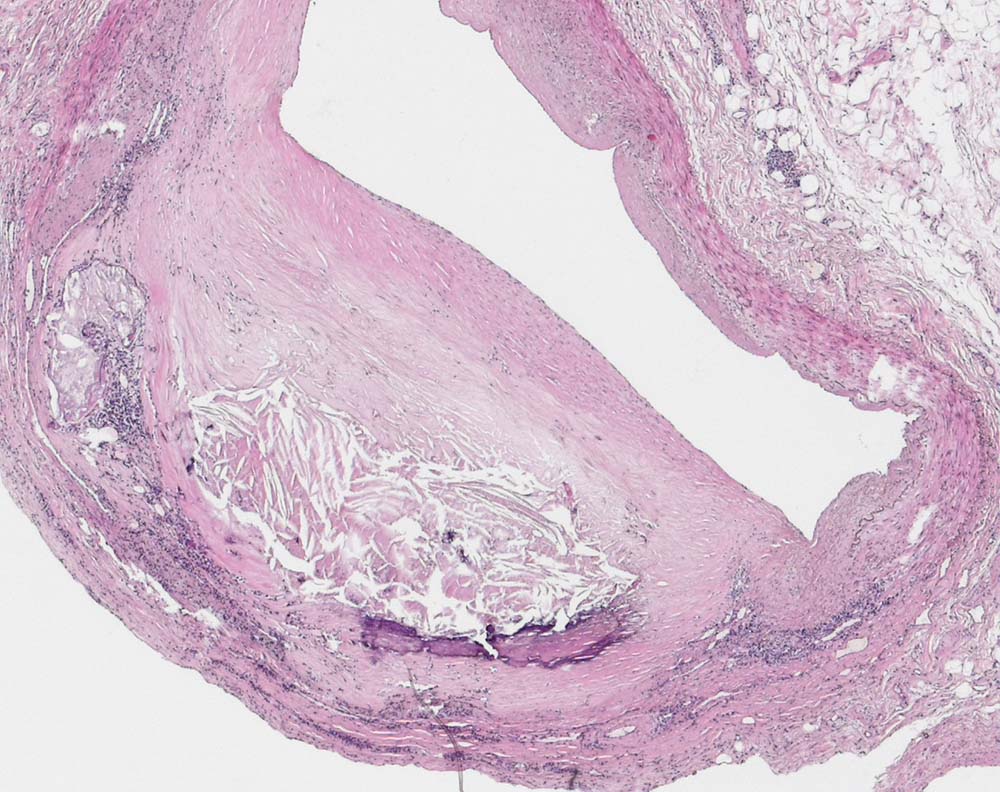

Воспаление бляшки